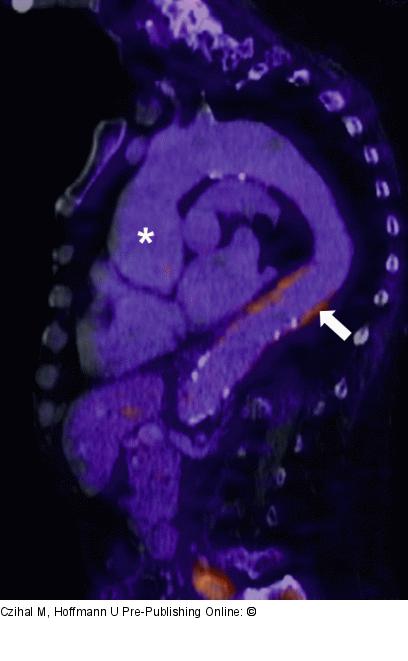

Abbildung 2: Riesenzellarteriitis 18-FDG-PET-CT einer 69-jährigen Patientin mit langjährig bestehender, steroidrefraktärer extrakranieller Riesenzellarteriitis. Unter Therapie persistierende Inflammation der Aorta descendens (Pfeil) sowie Aneurysma der Aorta ascendens (*). Nebenbefundlich ausgeprägter Rundrücken bei steroidinduzierter Osteoporose. |

Abbildung 2: Riesenzellarteriitis

18-FDG-PET-CT einer 69-jährigen Patientin mit langjährig bestehender, steroidrefraktärer extrakranieller Riesenzellarteriitis. Unter Therapie persistierende Inflammation der Aorta descendens (Pfeil) sowie Aneurysma der Aorta ascendens (*). Nebenbefundlich ausgeprägter Rundrücken bei steroidinduzierter Osteoporose. |